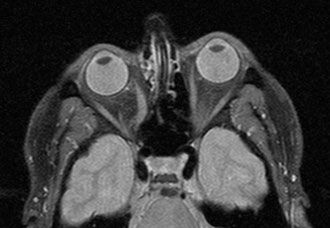

Bei Beschwerden im Bereich der Augen oder Sehstörungen liefert die MRT der Orbita wertvolle Einblicke in die Strukturen von Sehnerv, Augenmuskeln und umliegendem Gewebe.

Sie wird häufig eingesetzt zur Diagnose von Sehnerventzündungen (Opticusneuritis), die oft im Zusammenhang mit Multipler Sklerose auftreten, oder bei endokriner Orbitopathie (Morbus Basedow). Auch Tumoren wie das Opticus-Meningeom oder Fehlstellungen der Augenmuskulatur können mit der MRT präzise beurteilt werden.